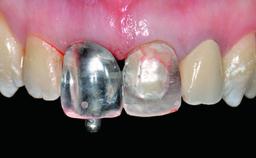

Defining Characteristics One missing tooth to be replaced by an implant-borne crown

Loading Protocol Conventional or early

Retention Screw-retained Screw-retained

Provisional Implant-Supported Prosthesis Prosthodontic margin > 3 mm apical to mucosal margin Prosthodontic margin > 3 mm apical to mucosal margin

Interim Prosthesis during Healing Fixed Fixed